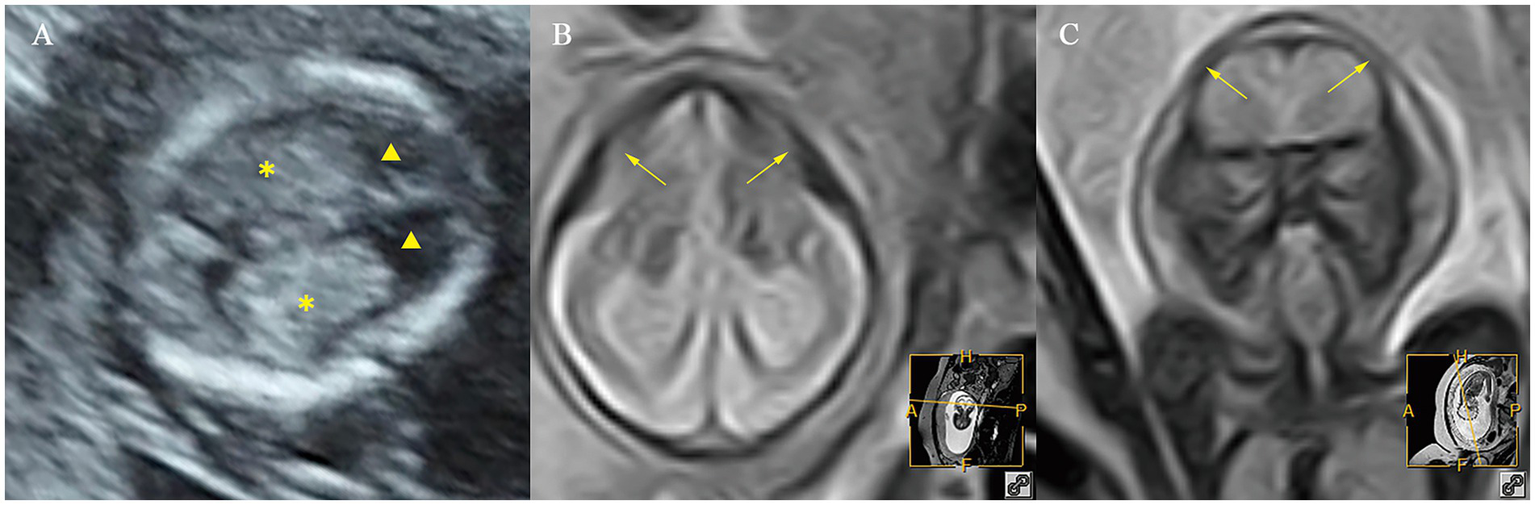

A total of 10/11 (90.9%) cases in the fetuses with microcephaly had CPA/HA ratio > 95th centile, 6/11 (54.5%) cases had CPL/OFD ratio > 95th centile, and 7/11 (63.6%) cases had HC/AC ratio < 5th centile. A total of 2/11 (18.2%) cases had abnormalities in the CFD/OFD ratio, including one case with a CFD/OFD ratio > 95th centile and one case with a CFD/OFD ratio < 5th. Fetuses with microcephaly showed a significantly higher CPA/HA ratio (p < 0.001), higher CPL/OFD ratio (p < 0.001), and lower HC/AC ratio (p < 0.05); the difference in CFD/OFD ratio did not reach statistical significance (p > 0.05) (Figure 6).

Figure 6

Ultrasound and MR images of a fetus with microcephaly at early and mid-gestation. (A) Ultrasound images at early gestation. (B,C) MR images at mid-gestation. ▲, the lateral ventricles; ✽, the choroid plexus; ⟶, abnormal cranial morphology.